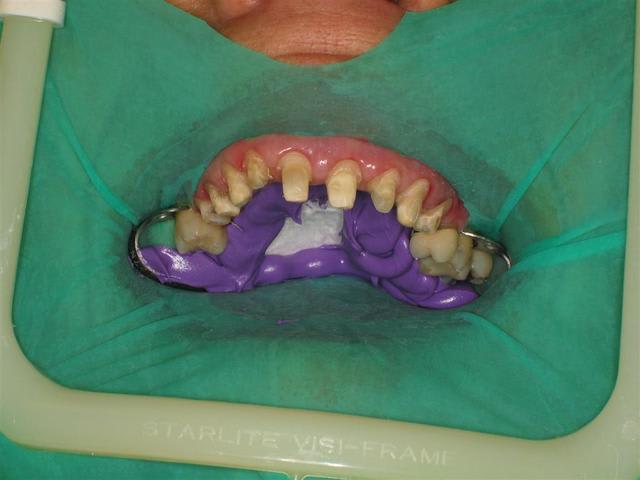

Même et surtout pour les cas complexes (essai et cimentation de 6 à 10 unités céramique)la digue est un outil très utile. Je peux etcher, placer l'adhésif, prendre mon temps pour coller sans avoir la langue, la salive etc.